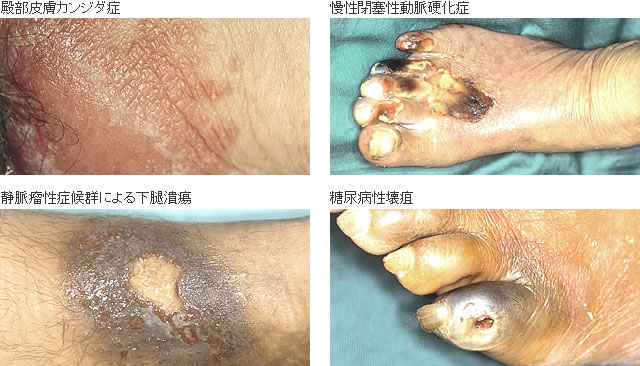

褥瘡治療① 実はあまり知られていない必須の褥瘡知識:褥瘡の治療法は深さによって異なる! -皮膚科専門医が伝授!医療従事者のための高齢者皮膚トラブル対策講座。

褥瘡治療① 実はあまり知られていない必須の褥瘡知識:褥瘡の治療法は深さによって異なる! -皮膚科専門医が伝授!医療従事者のための高齢者皮膚トラブル対策講座。

内科医に役立つ皮膚科の知識 褥瘡臨床雑誌内科 105巻4号医書.jp。